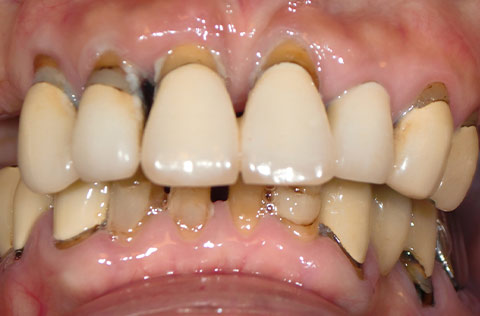

奥歯がなく、前歯は重度の歯周病だった。インプラントを含む包括的治療で、審美性と機能を回復したケース。

上あご前歯の咬耗と、左奥歯が全部欠損しているケース。インプラントを含む包括的治療で、見た目と機能を回復した。